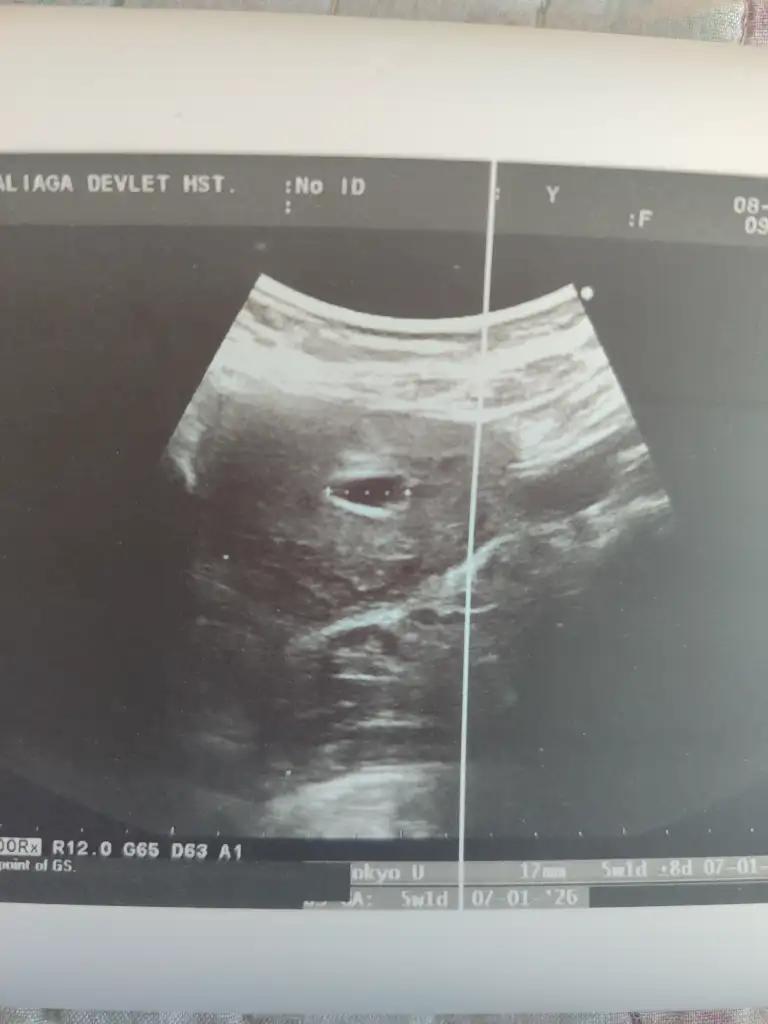

Yani ben de onu anlamadım çünkü keseye ben de baktığımda gayet büyük duruyor hatta resimde bile var ilk sayfaya girersen görebilirsin canım yani benim tabirimce 5 haftalık gibi durmuyor orada 17 milim yazıyordu sonuçta herhalde kesenin boyutu 17 milim işte aldım randevu çarşamba günü gideceğim nasip olursa başka bir doktora

Selam kızlar bugün ilk kontrolüme gittim doktor kese var ama bebek yok dedi 2 hafta sonra tekrar gel dedi keseye göre 5+1'miş ama son adet tarihim 14 Mart'ta muhtemelen geç döllenme olmuş yani canım sıkılmadı değil kese gayet iyi güzel yolk saç görünüyor ama şu an bebeği göremedim dedi ama sanki köşede ben görüyorum gibi sizce de öyle değil mi uzun bakmadı biraz daha uzun baksaydı belki görebilirdi karından baktı bu arada eşim de başka bir doktora randevu al dedi haftaya çarşamba başka bir doktor için randevu aldım bakalım siz de bir bakar mısınız kızlar normal mi bu ikinci resimde eklediğim kırmızı çizgi alan içerisinde sanki var olarak görüyorum sizce de öyle değil mi